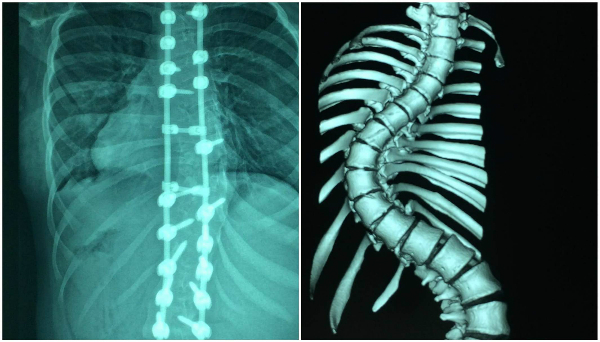

Cột sống bệnh nhân sau khi phẫu thuật và trước đó.

Ngày 26/12/2017, các bác sĩ tiến hành cuộc phẫu thuật kéo dài 6,5 giờ để nắn chỉnh, hàn xương giúp thay đổi hình dạng cột sống. Bé được bắt 21 ốc, 2 thanh nối dọc, 2 thanh nối ngang để cố định cột sống. Bệnh nhân mất khoảng 850 ml máu, được sử dụng kỹ thuật truyền máu hoàn hồi, sử dụng lại chính lượng máu đã mất để truyền.

"Thường cột sống cong trên 100 độ, tỷ lệ nắn chỉnh đạt được trên 40% là tốt. Trường hợp này bệnh nhân được nắn chỉnh, sửa chữa trên 64%", giáo sư Thành phân tích. Chiều cao bệnh nhân tăng thêm 7 cm, từ 1,48 m trước mổ lên 1,55 m.